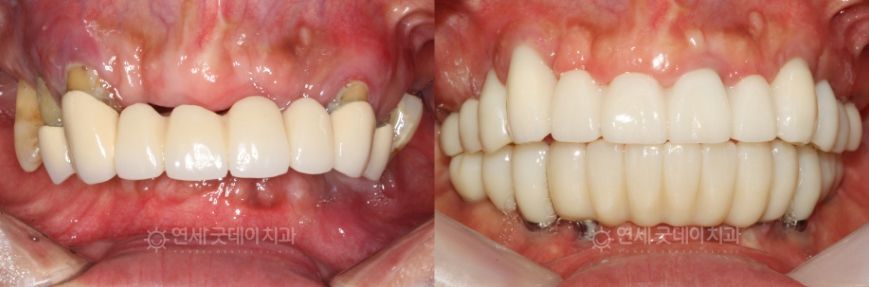

Case Review

Full Mouth Implant Before & After